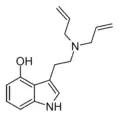

| 4-HO-DALT | artificial | 4-OH | H2C=CH-CH2 | H2C=CH-CH2 | 4-hydroxy-N,N-diallyltryptamine | |